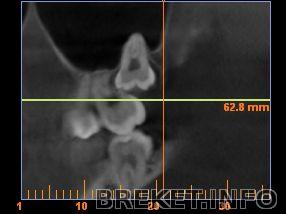

ИринаМ да если бы это было так просто - я бы тоже удалила (что и сделала с единственной выросшей, списав её якобы из-за кариеса, а по факту - нах мне зуб, растущий в щёку, не участвующий в жевании и чувствительный при чистке?) Но как вот удалить вторую верхнюю? Удалив ради нее и 7ку? Так вообще без зубов остаться можно, и так нет 4ок и 5ки... Хирург ведь заставил снимок делать, даже 6-месячной давности не принял, по свеженькому посмотрел и показал линейкой путь выхода зуба при удалении, и что четверть зуба в семерке (в корнях, частично их рассосав), и удалить можно только через нее. Ну верхняя ещё ладно, она нашла себе положение и, можно сказать, "выросла", просто неправильно, он обещал что дальше она не поползет, корни сформированы, коронка частично вылезла из десны. Про то что она в гайморовой пазухе корнями вообще молчу...

Но нижние... Угол челюсти маленький - а значит, либо челюсть еле открыта, освобождая доступ к зубу но так никаким инструментом не подлезешь, либо рот открыть шире чтоб можно было подлезть - но так к зубу не подступиться... Плюс корни на нерве лежат, что чревато его повреждением (как это хреново можно не говорить, да?)

Вот, нашла фотки с томограммы, видно что корни прям чуть ли не в нерве...